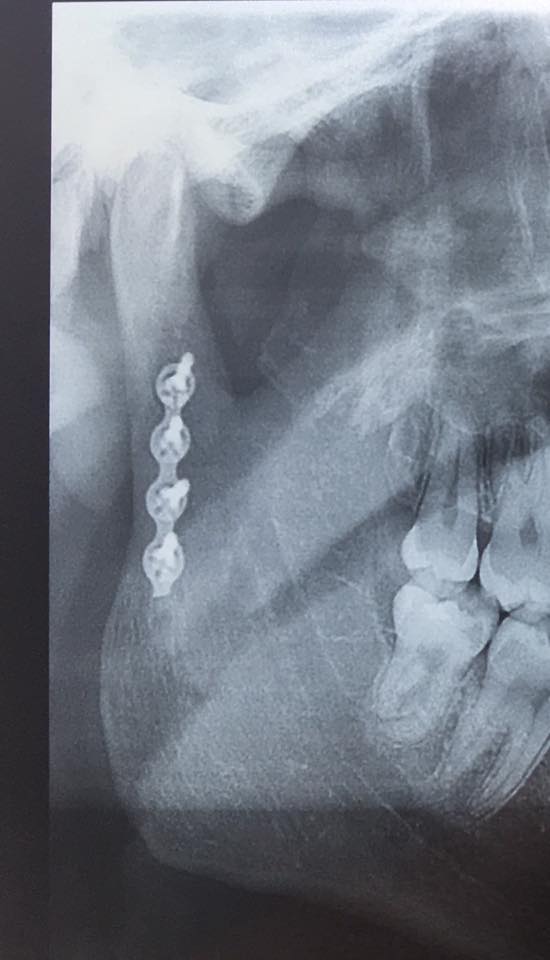

Intervenția prin care mandibula pacientului a fost refăcută cu ajutorul imprimantei a fost o premieră

Medicii au refăcut fața unui pacient prin tehnologia 3D. Intervenția a durat… 11 ore!